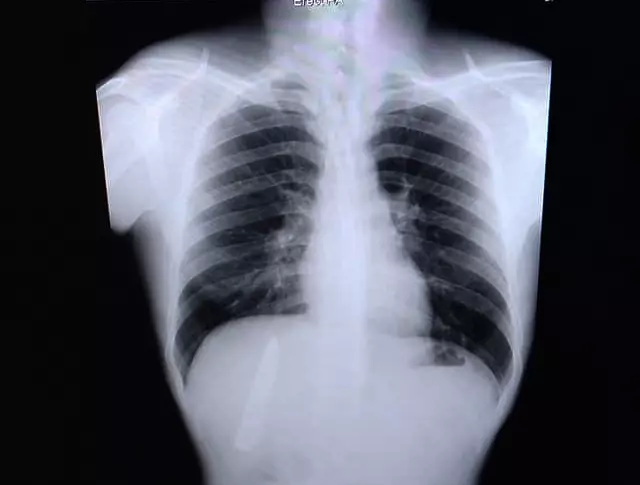

A Filipino man was unaware he had a knife stuck on his chest for more than a year. Kent Ryan Tomao, 36, was attacked and stabbed while walking home from work in Kidapawan City, the Philippines, in January last year. Bungling medics treated him but instead of removing the knife, they simply sewed up the wound leaving the broken-off blade stuck in his chest. Shockingly, Kent had the weapon lodged next to his rib cage just inches from piercing his lungs for more than a year before it was discovered during a health check for a new job on Tuesday (March 23). Kent is now furious that the doctors missed the four-inch-long knife blade and is demanding they remove it properly so he can start work as a miner, as his new employers believe it is not safe for him to go down pits with the knife inside him. He said: 'The doctors did not check my wounds properly last year so I believe they are partly at fault about what happened. They should fix this.' The worker claimed that the doctors only stitched his wounds to stop them from bleeding at the hospital. He was given painkillers and sent home. Fourteen months later Kent was hired at a mining company in nearby province Agusan del Sur and he was set to start next month. The company required a pre-employment medical test but an x-ray examination found the knife pointing upwards and stuck in his rib cage. Kent said his chest was sometimes painful during the cold weather but everything was tolerable and he never believed there was a serious problem. He said: ‘I always wondered why I felt pain in my chest when the weather was cold. But I had no idea there is a knife in my chest. 'The pain was never bad enough to even go to see a doctor. I just waited for the pain to pass. Now I'm relieved that I know the real problem.' The worker will have to undergo an operation to remove the knife before he can start working but he said he doesn�,Image: 600944390, License: Rights-managed, Restrictions: , Model Release: no

A Filipino man was unaware he had a knife stuck on his chest for more than a year. Kent Ryan Tomao, 36, was attacked and stabbed while walking home from work in Kidapawan City, the Philippines, in January last year. Bungling medics treated him but instead of removing the knife, they simply sewed up the wound leaving the broken-off blade stuck in his chest. Shockingly, Kent had the weapon lodged next to his rib cage just inches from piercing his lungs for more than a year before it was discovered during a health check for a new job on Tuesday (March 23). Kent is now furious that the doctors missed the four-inch-long knife blade and is demanding they remove it properly so he can start work as a miner, as his new employers believe it is not safe for him to go down pits with the knife inside him. He said: 'The doctors did not check my wounds properly last year so I believe they are partly at fault about what happened. They should fix this.' The worker claimed that the doctors only stitched his wounds to stop them from bleeding at the hospital. He was given painkillers and sent home. Fourteen months later Kent was hired at a mining company in nearby province Agusan del Sur and he was set to start next month. The company required a pre-employment medical test but an x-ray examination found the knife pointing upwards and stuck in his rib cage. Kent said his chest was sometimes painful during the cold weather but everything was tolerable and he never believed there was a serious problem. He said: ‘I always wondered why I felt pain in my chest when the weather was cold. But I had no idea there is a knife in my chest. 'The pain was never bad enough to even go to see a doctor. I just waited for the pain to pass. Now I'm relieved that I know the real problem.' The worker will have to undergo an operation to remove the knife before he can start working but he said he doesn�,Image: 600944403, License: Rights-managed, Restrictions: , Model Release: no

A Filipino man was unaware he had a knife stuck on his chest for more than a year. Kent Ryan Tomao, 36, was attacked and stabbed while walking home from work in Kidapawan City, the Philippines, in January last year. Bungling medics treated him but instead of removing the knife, they simply sewed up the wound leaving the broken-off blade stuck in his chest. Shockingly, Kent had the weapon lodged next to his rib cage just inches from piercing his lungs for more than a year before it was discovered during a health check for a new job on Tuesday (March 23). Kent is now furious that the doctors missed the four-inch-long knife blade and is demanding they remove it properly so he can start work as a miner, as his new employers believe it is not safe for him to go down pits with the knife inside him. He said: 'The doctors did not check my wounds properly last year so I believe they are partly at fault about what happened. They should fix this.' The worker claimed that the doctors only stitched his wounds to stop them from bleeding at the hospital. He was given painkillers and sent home. Fourteen months later Kent was hired at a mining company in nearby province Agusan del Sur and he was set to start next month. The company required a pre-employment medical test but an x-ray examination found the knife pointing upwards and stuck in his rib cage. Kent said his chest was sometimes painful during the cold weather but everything was tolerable and he never believed there was a serious problem. He said: ‘I always wondered why I felt pain in my chest when the weather was cold. But I had no idea there is a knife in my chest. 'The pain was never bad enough to even go to see a doctor. I just waited for the pain to pass. Now I'm relieved that I know the real problem.' The worker will have to undergo an operation to remove the knife before he can start working but he said he doesn�,Image: 600944414, License: Rights-managed, Restrictions: , Model Release: no